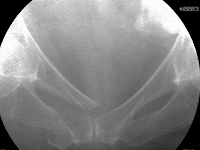

Her detailed neurological examination was otherwise normal. Pelvic plain radiographs and a computed tomography scan identified a right-sided displaced pubic ramus fracture and a displaced Y-shaped sacral fracture. On the anteroposterior image, she had a paradoxical inlet appearance of the sacrum.

U, Y, and H-shaped sacral fractures are unusual and are often delayed diagnoses. The AP pelvic plain film may demonstrate a paradoxical inlet of the sacrum when the upper sacral component is displaced and kyphotic. Mid-sagittal sacral CT imaging better defines the fracture details. Percutaneous pelvic fixation is used when the fracture fragments and therefore osseus fixation pathways are adequately reduced/realigned.